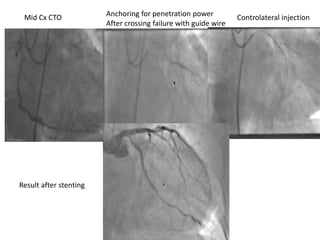

Mid Cx CTO

Fielder XT and Gaia second do not cross the lesion

Progress 200 T with Anchoring balloon in first MB

Allows increase of penetration power of guide wire

Crossing of the CTO

Contro lateral injection to check

guide wire position in true lumen Final Result